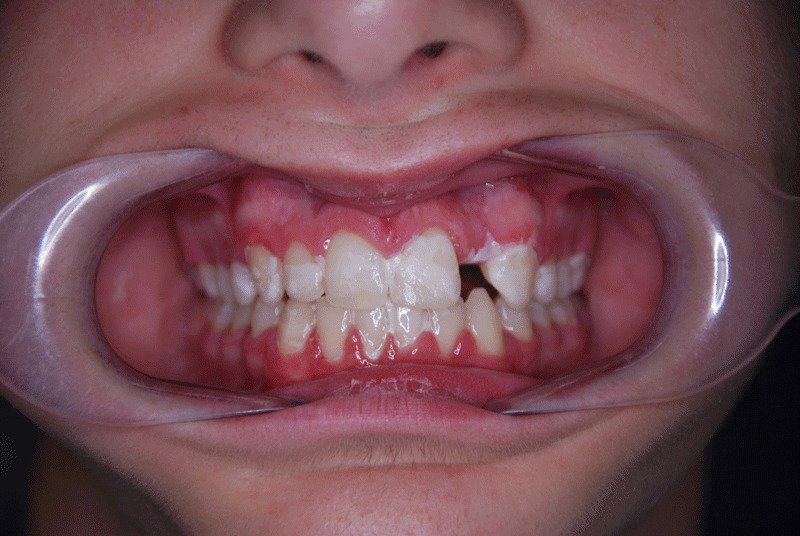

Overbite before and after

In children, deep bite is corrected with interceptive orthodontics. To avoid excessive wear, it is ideal to start treatment between approximately five and nine years of age.  Fixed orthodontic treatment is performed to correct it during adolescence, since at that age it is too late for an interceptive treatment option.

To correct the overbite, the case of the child or young person should be studied through a study to assess the type and time necessary for treatment. Therefore, whether it is interceptive or fixed orthodontics, it will depend on the degree and type of overbite and the age of the patient.